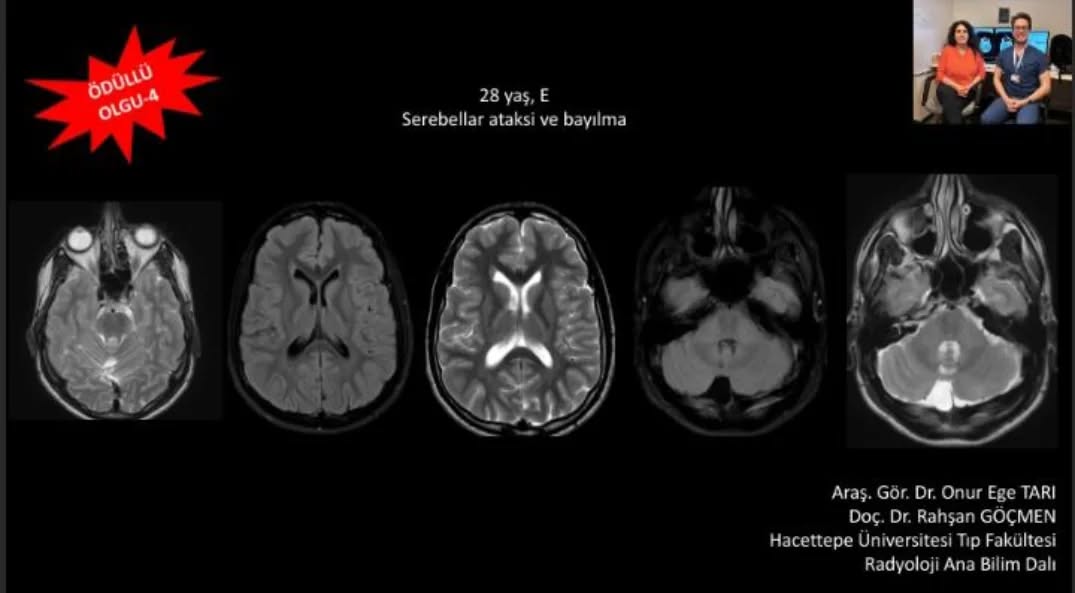

📣📣📣Haftanın ödüllü olgu sorusu yayınlandı.

Yanıtlarınızı www.tnrd.org.tr adresinden bekliyoruz.